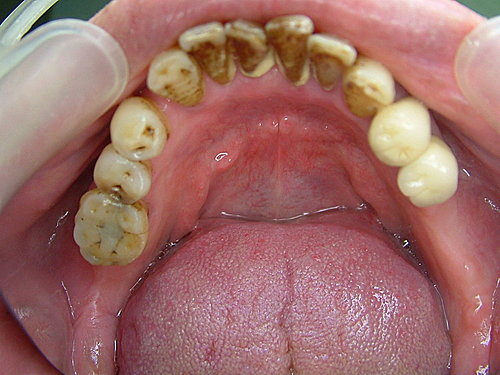

下顎咬合面觀 ..... 右下缺了兩顆大牙 左下只有一顆大牙 咀嚼效率差

牙結石厚 先洗牙清乾淨再說 .....